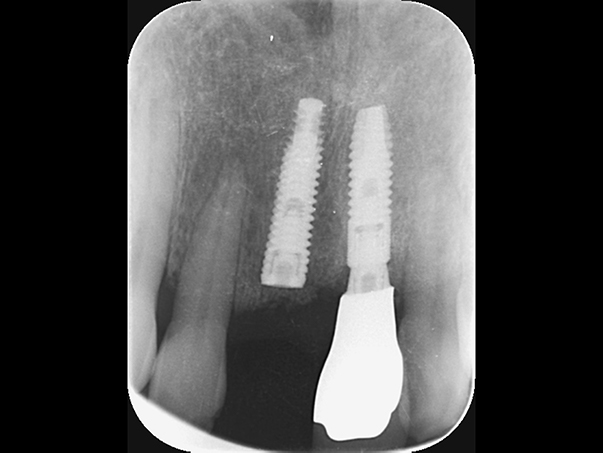

インプラント予定部位の骨の状態。 骨のてっぺんの部分は骨が薄く、また、横には大きな穴があいている状態。 これではインプラントを埋めてもしっかり入らずに、骨から飛び出してしまう。

麻布十番歯科のインプラント予定部位の骨の状態の症例写真

そのため、骨をてっぺんと穴の空いた部分に作る。 そのために、人工の骨をおき、チタンのメッシュで固定する。 この状態で6ヶ月ほど待機する。

麻布十番歯科のインプラント治療で人工の骨をおき、チタンのメッシュで固定している症例写真

6ヶ月後再び歯茎を切り中の状態を確認。骨がしっかりできており、インプラント手術を行えることが分かると思う。 インプラントを埋めるための穴をあけて、インプラントを埋入した。

麻布十番歯科のインプラント手術の症例

麻布十番歯科のインプラント手術の症例① 麻布十番歯科のインプラント手術の症例② 麻布十番歯科のインプラント手術の症例③